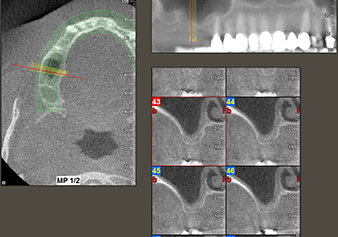

A 49-year-old female patient, a non-smoker and with nothing remarkable in her general medical history, was referred to our oral surgery practice for surgical extraction of tooth 16 and subsequent implantation. After the extraction, the patient experienced mild sinusitis trouble with the resultthat we initially waited six months before carrying out the measure. The residual bone height at the planned implant position measured 3-4 mm (Fig. 1 and 2).

Following an intermediate check (Fig. 4) a further preparation step was performed (Fig. 5). Afterwards, the hydraulic Z35P instrument was used to lift the membrane to the desired position (Fig. 6 and 7). This was followed by further piezosurgical preparation of the implant bed, concluded with a rotary bur and shoulder milling cutter up to the implant diameter of 4.8 mm. Before the implant was inserted, the augmentation material (particle size approx. 0.8-1.6 mm) was introduced underneath the Schneiderian membrane (Fig. 8).